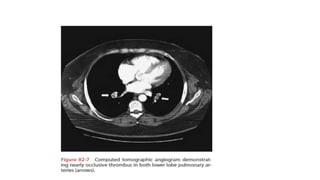

Role of CT Pulmonary Angiogram- MDCT with

contrast

• At the present time, CT is considered confirmatory in excluding

embolism in patients with a low or intermediate likelihood of disease

and confirming embolism in patients with intermediate or high

probability of disease.

Role of CTPulmonary Angiogram- MDCT with contrast • At the present time, CT is considered confirmatory in excluding embolism in patients with a low or intermediate likelihood of disease and confirming embolism in patients with intermediate or high probability of disease. • When discordance exists between the clinical assessment and CT findings, additional studies should be performed. • It is possible this recommendation will change as studies with 64- MDCT scanners are published.